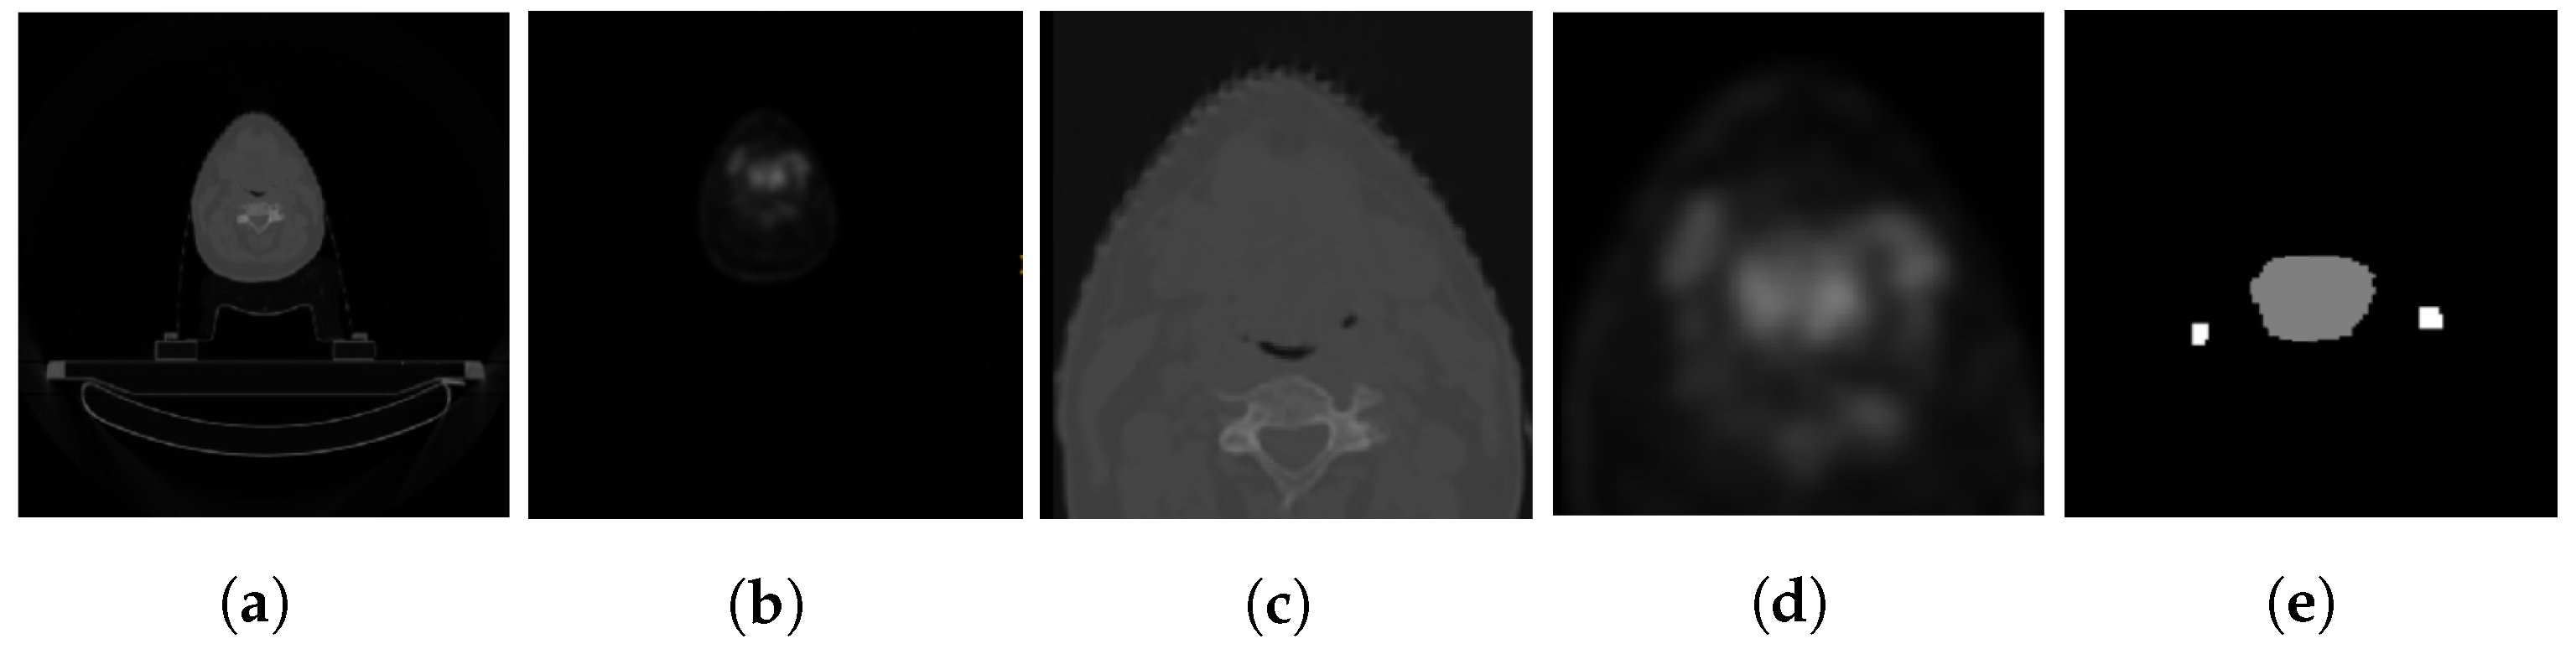

- We showcase the efficacy of the proposed method on multi-class segmentation of head and neck cancer tumors using multi-channel computed tomography (CT) and positron emission tomography (PET) scans of patients obtained from multi-center (seven centers) sources.

3.1. Dataset